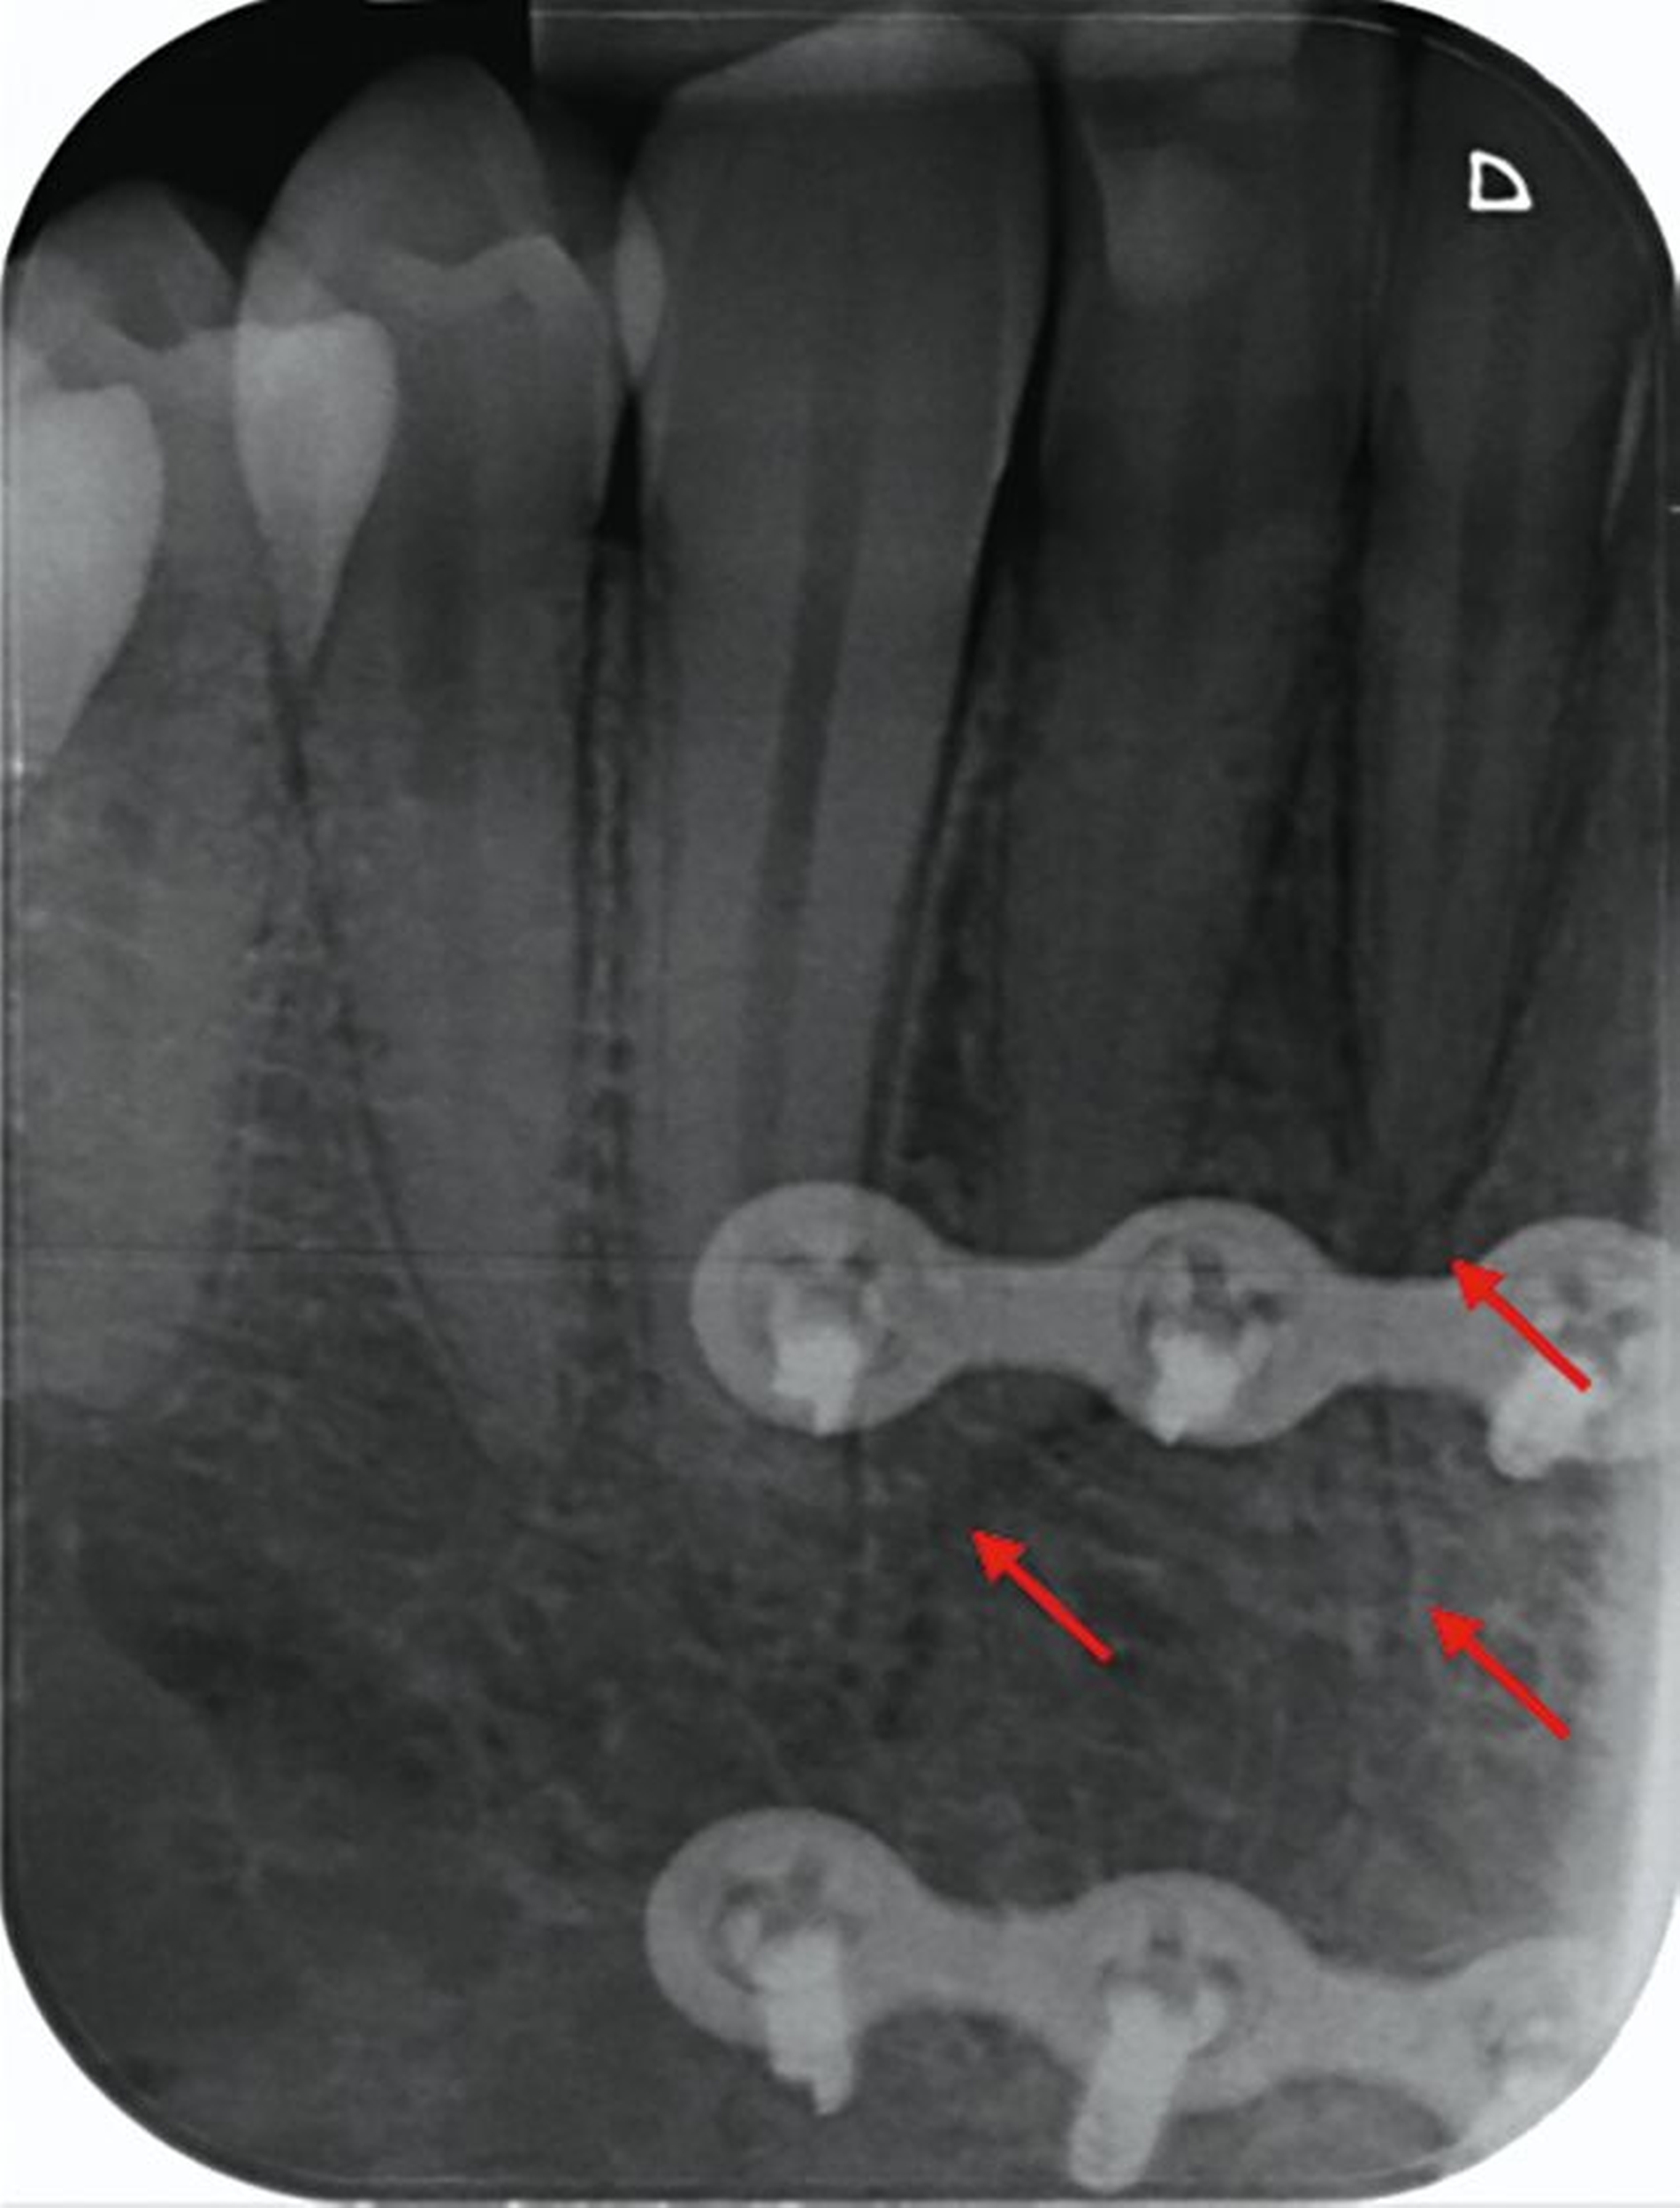

Zunächst wurden Einzelbildaufnahmen der Zähne 24, 26, 35, 33–43 angefertigt. Dabei fiel eine transluzente Frakturlinie ausgehend vom mesialen Parodontalspalt des 41 auf, die sich nach apikal-distal bis zum Apex des 42 darstellte (Abbildungen 3 und 4). Für einen radiologischen Überblick, mit dem auch eine Kiefergelenksfraktur ausgeschlossen werden kann, wurde eine Panoramaschichtaufnahme herangezogen (Abbildung 5). Darauf bildete sich eine unscharfe, C-förmige Transluzenz apikal der Zähne 31 und 41 ab. Eine genaue Beurteilung war nicht möglich, da der Bereich apikal der Unterkieferfront außerhalb der Bildebene lag. Die Processus coronoidei und condylares stellten sich beidseits unauffällig dar. Die Verdachtsdiagnose lautete: Unterkieferfraktur, unkomplizierte Kronenfrakturen an den Zähnen 26 und 35 sowie eine Längsfraktur an Zahn 24.

Nach einem Monat stellte sich der Patient für eine klinische und röntgenologische Nachkontrolle vor (Abbildungen 8 und 9). Nach der operativen Frakturversorgung hatte sich die Okklusion normalisiert und die Bewegung des Unterkiefers war weder schmerzhaft noch eingeschränkt. Die Zähne 41 und 42 zeigten einen Lockerungsgrad I und reagierten auf Kälte nicht sensibel. Dies erhärtete den Verdacht auf eine Dislokationsverletzung mit begleitendem Pulpainfarkt als Folge des Sturztraumas.

Nach vier Monaten wurden die Osteosyntheseplatten entfernt. Die radiologische Nachkontrolle ergab eine vollständige Ausheilung der Fraktur ohne pathologische Veränderungen der betroffenen Unterkieferfrontzähne (Abbildungen 10 und 11). Klinisch lagen keine Lockerungen vor.